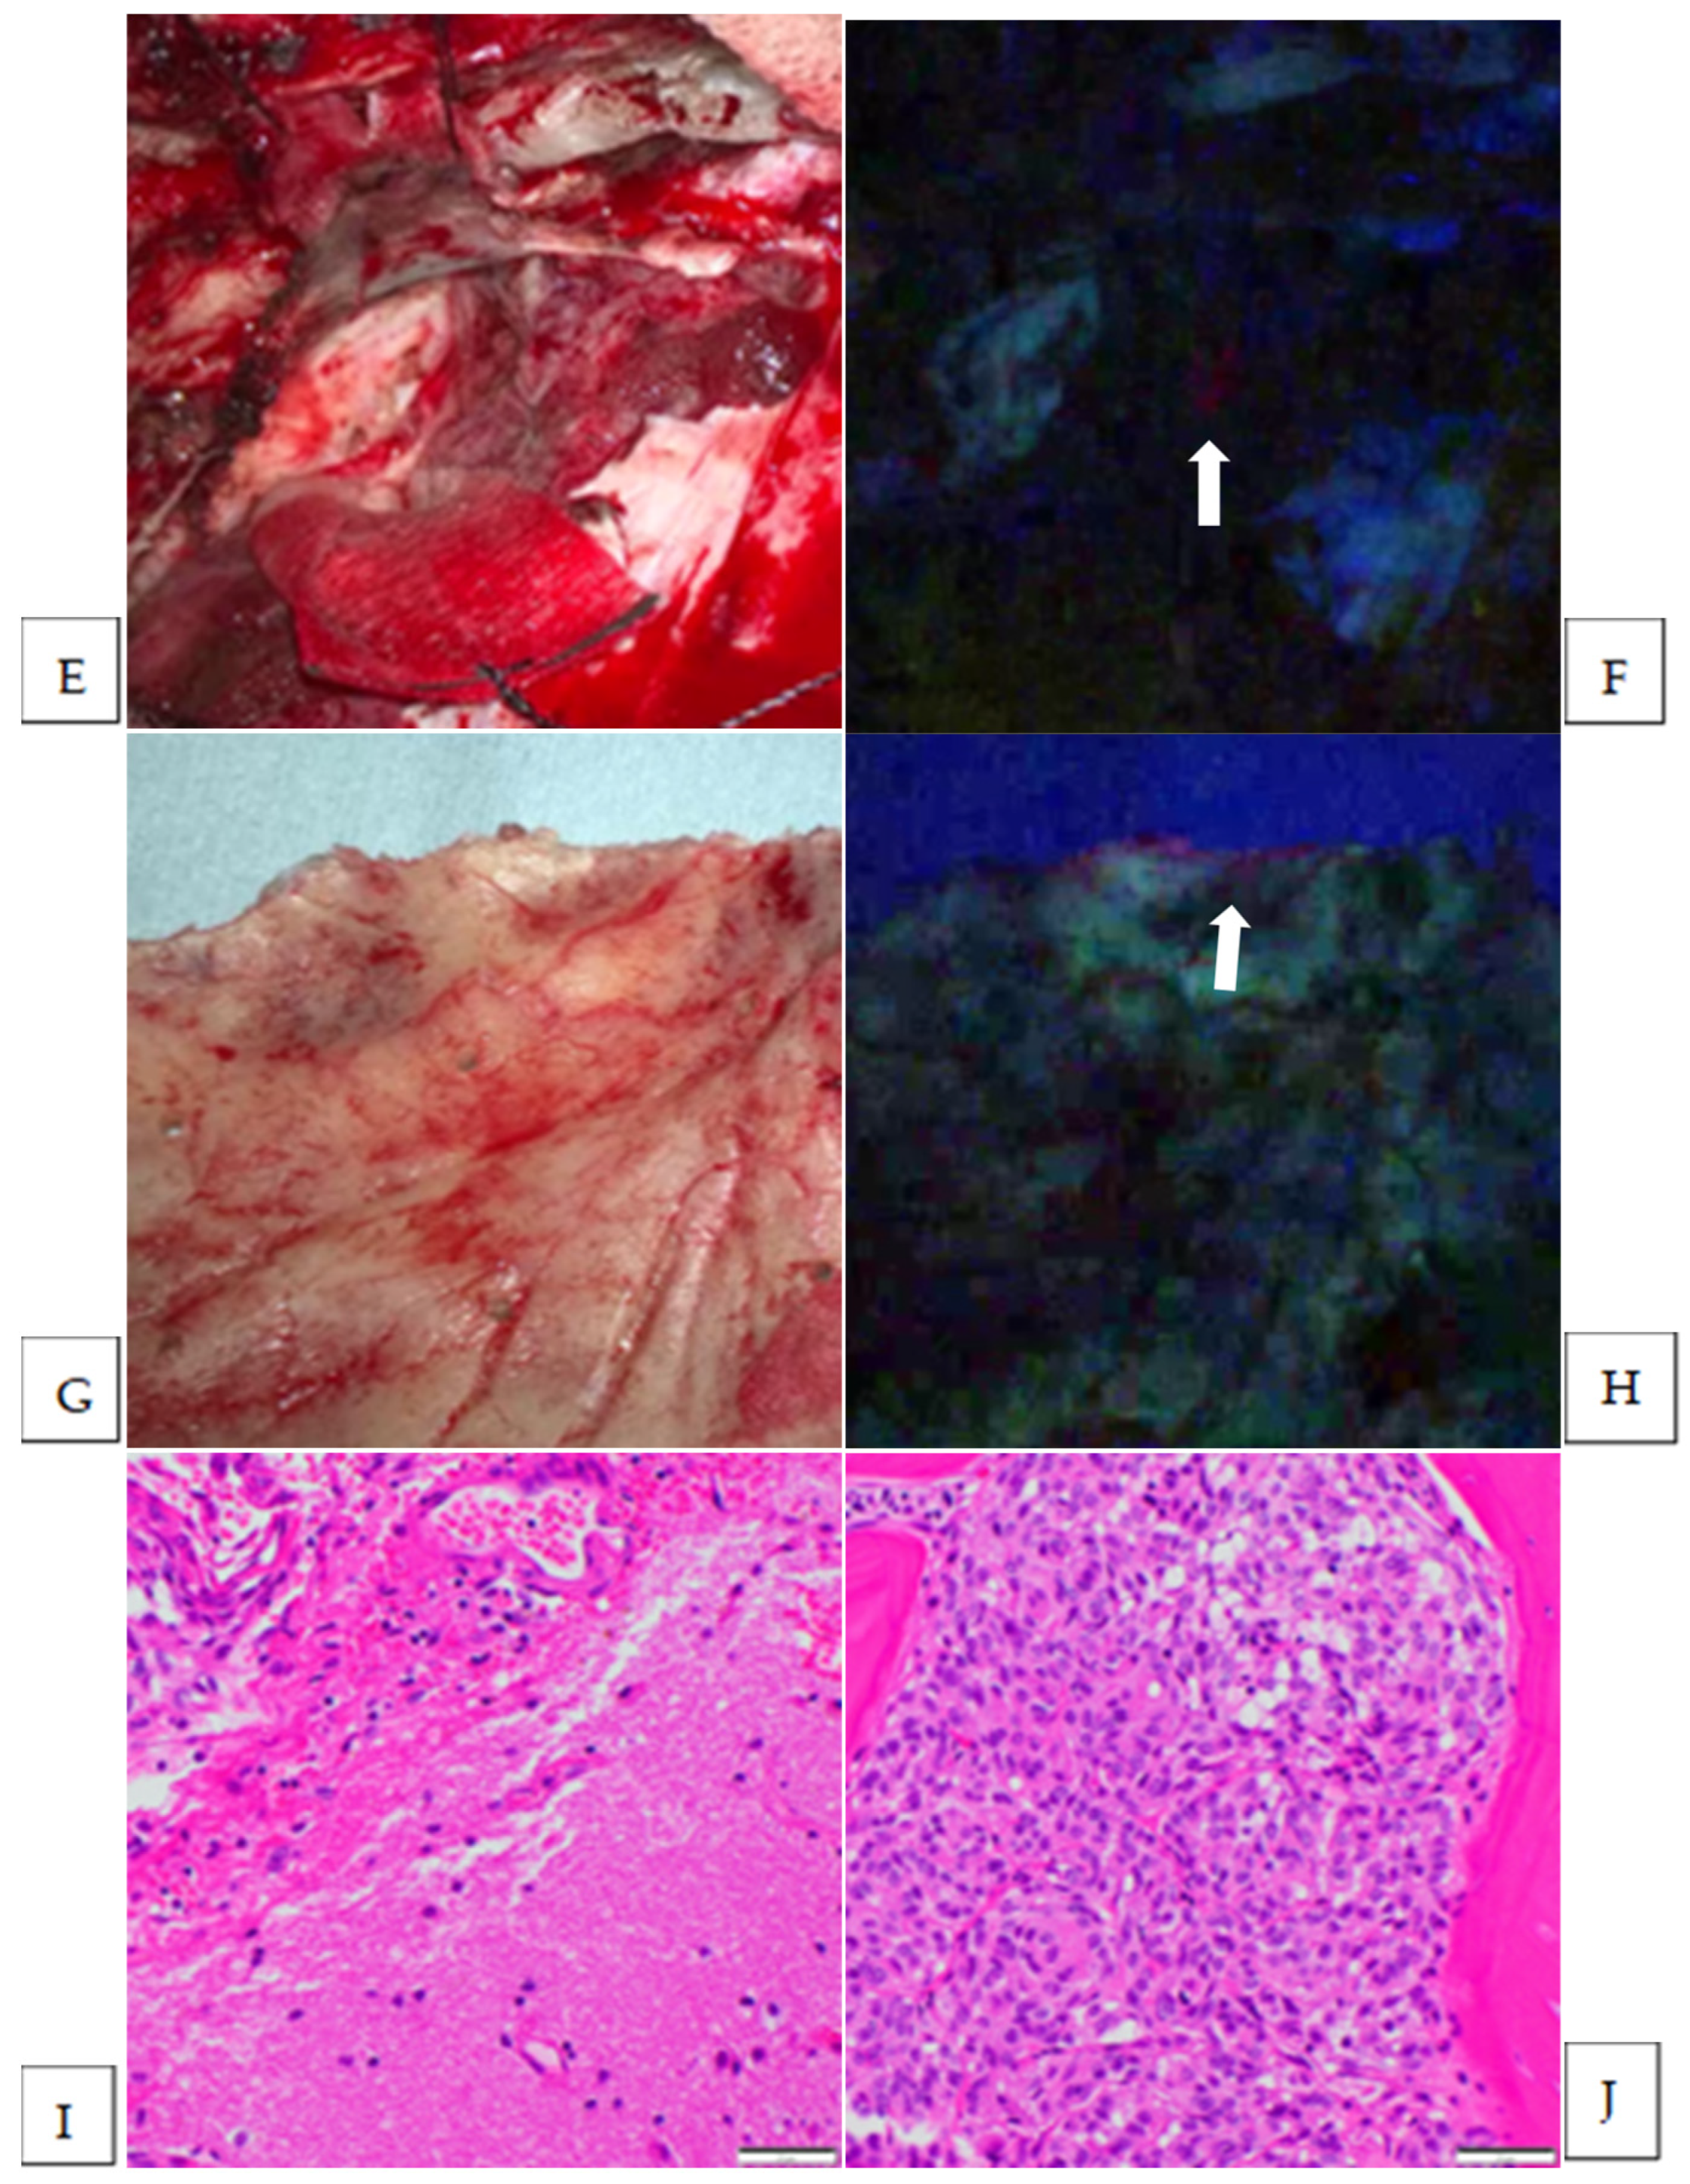

| 10 | sphenoid ridge | anaplastic | Strong | yes | yes | dura | 2 | NA |

| 11 | sphen-oorbital | meningothelial | Strong | yes | yes | bone | 1 | yes |

| 12 | convexity | transitional | Vague | yes | yes | brain | 1 | no |

| 13 | sphenoid ridge | transitional | Strong | yes | yes | brain | 2 | yes |